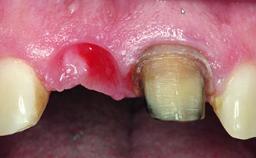

Replacement of an Upper Right Central Incisor with Root Resorption: Ridge Preservation, Early Placement of an RC Bone Level Implant

A 49-year-old female patient was referred for implant therapy to replace the upper right central incisor (tooth 11). The tooth had been assessed by an endodontist who diagnosed a vertical fracture of the root. The tooth had a hopeless prognosis and needed to be extracted. The patient was healthy and was not taking any medications. She was allergic to penicillin. The patient had high esthetic demands but her expectations were realistic. The extraoral examination revealed no facial asymmetries. The right temporomandibular joint demonstrated an opening click but was otherwise asymptomatic. The lip line was high with a significant gingival display.

Bone Volume Deficient vertically or deficient vertically AND horizontally